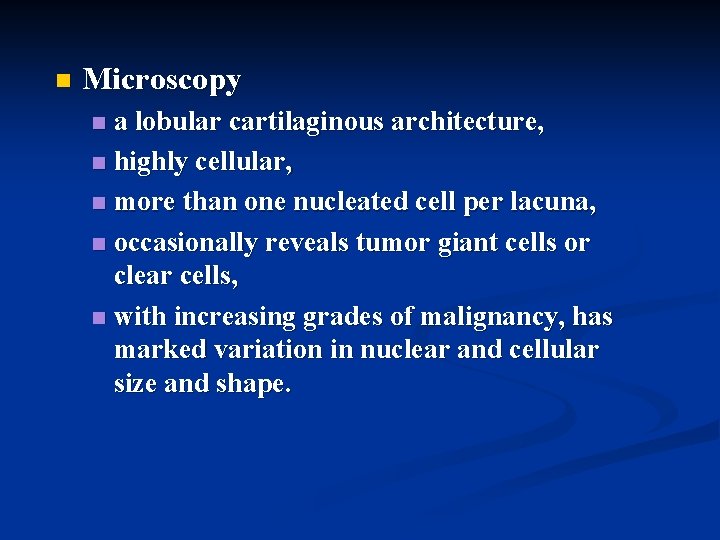

n Microscopy a lobular cartilaginous architecture, n highly cellular, n more than one nucleated cell per lacuna, n occasionally reveals tumor giant cells or clear cells, n with increasing grades of malignancy, has marked variation in nuclear and cellular size and shape. n